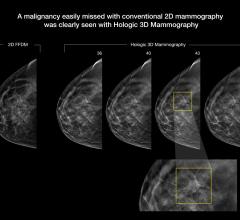

The digital breast tomosynthesis (DBT) market has evolved rapidly within the past year, with new vendors entering the market and recent clinical data continuing to support its use. In addition, the Centers for Medicare and Medicaid Services (CMS) created dedicated reimbursement codes for DBT procedures earlier this year.

Despite decades of progress in breast imaging, one challenge continues to test even the most skilled radiologists ...